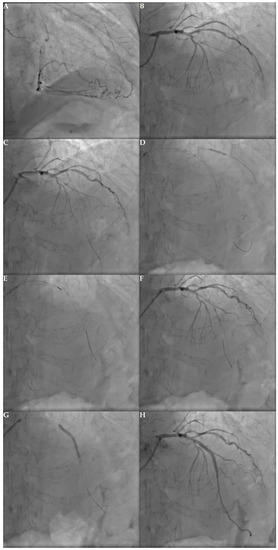

6.1. Antegrade

6.1.1. Antegrade Wire Escalation

6.1.2. Antegrade Dissection and Re-Entry

6.1.3. Parallel Wiring

6.2. Retrograde